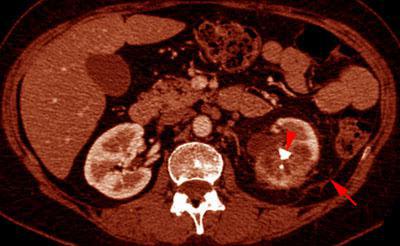

Pielonefritis xantogranulomatosa

VR seccional. Visión axial caudal. TC contrastado en fase venosa mostrando litiásis renal izquierda (punta de flecha) junto a cambios necroticos en su entorno. Obsérvense los cambios inflamatorios en fascia de Gerota (flecha) y espacio perirrenal